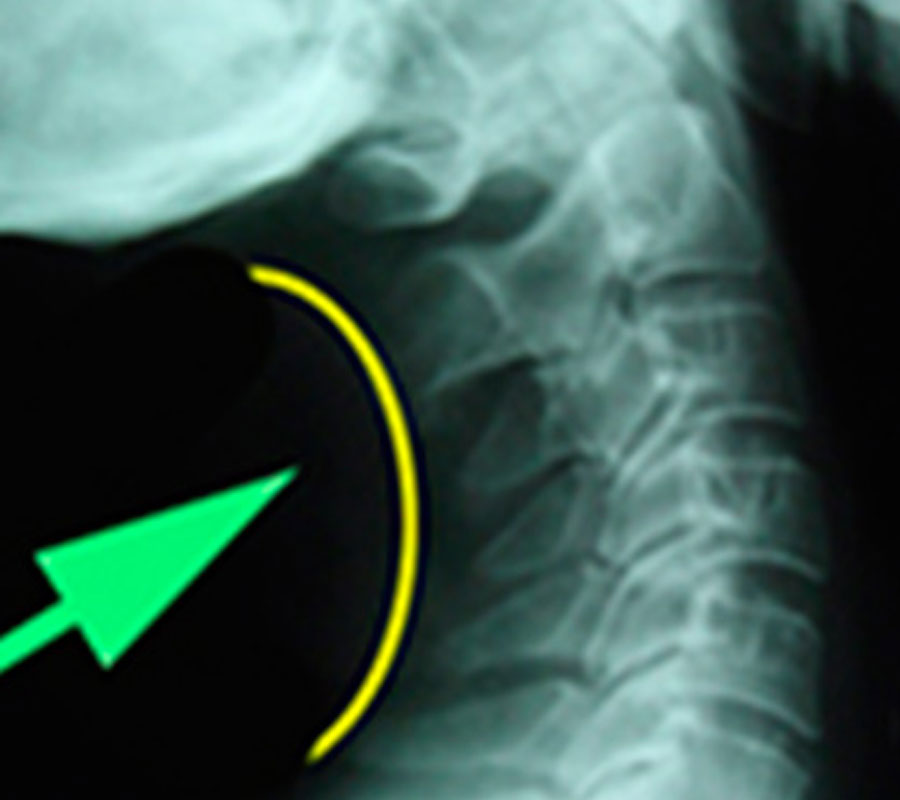

Estenosis

La estenosis, o estrechamiento, bien del canal medular (estenosis medular), o bien, de los agujeros intervertebrales por donde pasa la raíz nerviosa (estenosis foraminal), suele ser un proceso degenerativo. Factores como el sedentarismo o la obesidad pueden agravar los síntomas.